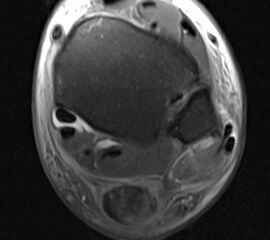

• Ggf. Magnetresonanztomographie des Rückfußes mit Kontrastmittel in Bauchlage und Plantarflexion des Fußes zur Beurteilung der Sehnen und des Bandapparates 20. Die Aussagekraft der MRT ist bezüglich gleichzeitiger Schäden der Sehnen gut. Die Instabilität selbst kann durch eine MRT Untersuchung nicht abschließend ausgeschlossen werden, da Untersuchung oft nicht im Stadium der akuten Luxation durchgeführt wird (Abbildung 3). Dagegen erlaubt die dynamische Untersuchung mit Ultraschall eine präzise Beurteilung der Sehnenstabilität 21.